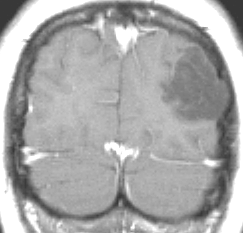

手術で症候性てんかんが完治した少女

10代の少女に見つかったDNTです。難治性のてんかんがあり1日になんども意識減損を生じて,けいれんを止める薬をたくさん飲んでいて副作用のために眠気で日常生活が困難でした。でも,他の症状は何もありませんでした。左の頭頂葉と側頭葉と後頭葉の境目にできたものです。おそらくお母さんのお腹の中いたときからあった腫瘍なので何もしないで様子を見てもいいのです。でも,てんかん発作がひどいので腫瘍だけを摘出しました。DNTだけを取っても後遺症が残ることはほとんどありません。この場所は周囲の脳組織をとると後遺症がでる場所 (eroquent area)なので,てんかんを止める目的でもかなりの理由がないと周囲の脳組織は摘出しません。この子は,抗てんかん薬もいらなくなって完治しました。